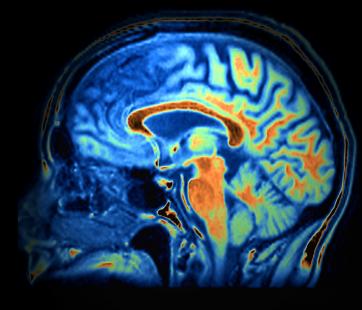

Déjà sous haute surveillance pour le haut risque de malformations du cerveau, du visage et du cœur chez l’enfant à naître lorsque le médicament est utilisé par la femme au cours de sa grossesse, l’isotrétinoïne orale fait l’objet d’une nouvelle alerte. L’enfant à naître pourrait en effet développer des troubles neuro-développementaux de type autistiques. L’ANSM a réalisé une revue des données disponibles sur ce risque à la suite de la déclaration au réseau national des centres de pharmacovigilance (CRPV) d’une suspicion de troubles autistiques chez un jeune enfant exposé pendant la grossesse de sa mère à l’isotrétinoïne et né sans malformation visible. Son comité scientifique permanent (CSP) Reproduction-Grossesse-Allaitement s’est prononcé en faveur d’un risque potentiel, avec ou sans malformation associée, en attendant que ce risque puisse être confirmé ou non par des investigations plus poussées. L’agence transmettra ses données à l’Agence européenne du médicament (EMA), ce risque potentiel n’étant pas, à ce jour, confirmé au niveau européen.

L’autorité sanitaire met dès à présent à disposition des professionnels de santé le rapport du CSP Reproduction-Grossess-Allaitement pour faciliter la discussion sur ce risque potentiel avec les patientes dont l’enfant a été exposé in utero à l’isotrétinoïne orale et qui souhaitent poursuivre leur grossesse. L’ANSM rappelle qu’en cas de découverte de grossesse, le traitement doit immédiatement être arrêté et la patiente adressée à un médecin spécialiste ou compétent en tératologie pour évaluation et conseil. Elle ajoute que « l’absence d’anomalie visible à l’échographie pendant la grossesse ou à la naissance ne permet pas d’anticiper que l’enfant ne présentera pas de troubles, notamment des troubles neuro-développementaux à type de retard mental ou de retard des fonctions motrices (équilibre, marche…) ».